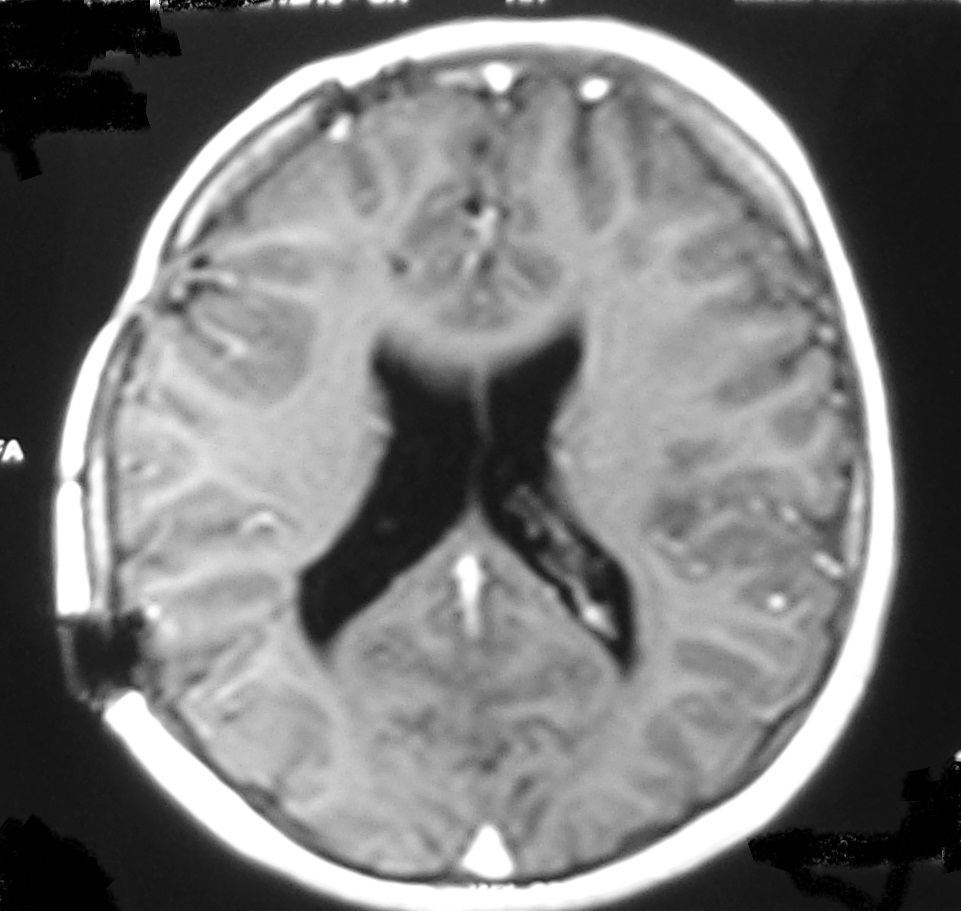

The signs and symptoms of shunt dysfunction are related to high intracranial pressure most commonly including headache, nausea, vomiting, bulge fontanel, irritability, sunset eye. Increased ventricular diameter in comparison to prior studies, increased temporal horns width, sulcus effacement and rounding of 3rd ventricle are common findings in neuroimaging studies during shunt malfunction (Figure 1). However, stable ventricular dimensions on serial imaging studies (Figure 2) may wrongly be interpreted as normal shunt function [4].

Figure 1: A. Surveillance brain MRI of a 12 year old boy with shunting due to brain tumor at age of 6. The lateral ventricles were nearly normal size and the child without any symptoms. B. The child admitted with headache vomiting and drowsiness. The brain CT scan confirms increased size of lateral ventricles with sulcus effacement.